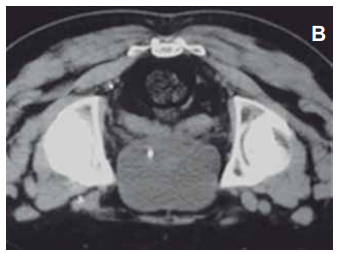

A imagem apresentada retrata a região da pelve, e é um estudo realizado em corte no plano